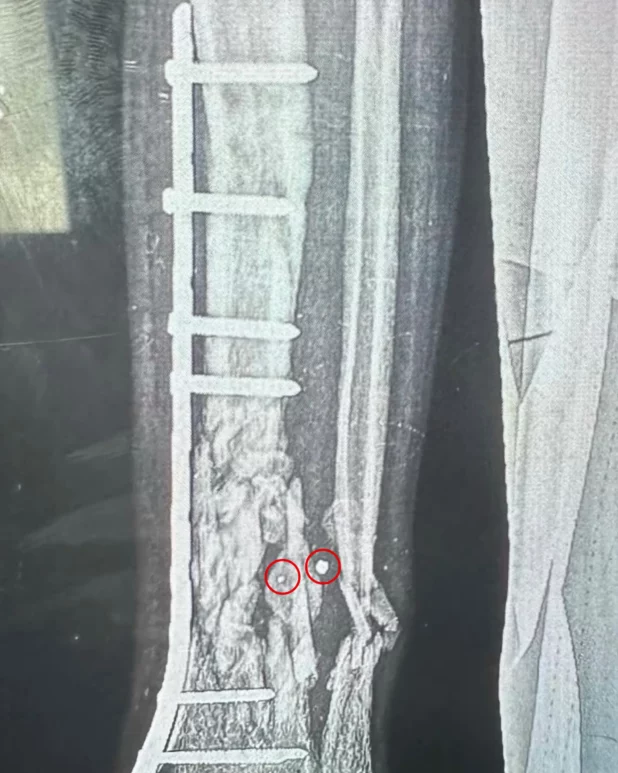

“By far the most common wounds are one or two millimetre entry and exit wounds,” he said.

“X-rays showed demolished bones with a pinhole wound on one side, a pinhole on the other, and a bone that looks like a tractor trailer drove over it. The children we operated on, most of them had these small entrance and exit points.”

Sanjay Adusumilli, an Australian surgeon who worked at the al-Aqsa hospital in central Gaza in April, recovered shrapnel made up of small metal cubes about three millimetres wide while operating on a young boy. He described wounds from fragmentation weapons distinguished by the shards of shrapnel destroying bone and organs while leaving just a scratch on the skin.

Explosives experts who reviewed pictures of the shrapnel and the doctors’ descriptions of the wounds said they were consistent with bombs and shells fitted with a “fragmentation sleeve” around the explosive warhead in order to maximise casualties. Their use has also been documented in past Israeli offensives in Gaza.

Ball said the metal cubes recovered by Adusumilli are typically found in Israeli-made weapons such as certain types of Spike missiles fired from drones. He said the doctors’ accounts of tiny entry wounds are also consistent with glide bombs and tank rounds fitted with fragmentation sleeves such as the M329 APAM shell, which is designed to penetrate buildings, and the M339 round which its manufacturer, Elbit Systems of Haifa, describes as “highly lethal against dismounted infantry”.